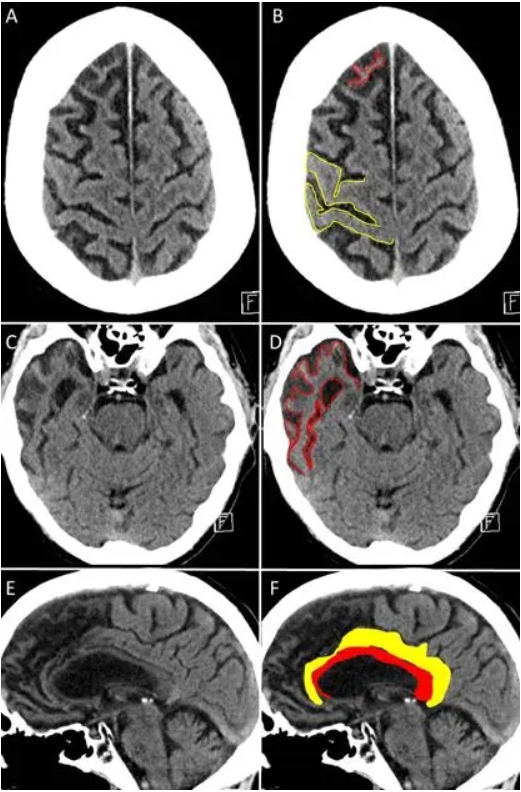

安德烈生前的脑部磁共振成像显示,他的大脑萎缩程度对于其年龄而言异常严重。然而,这种变化并不等同于“加速衰老”。在正常老龄化过程中,大脑结构的改变通常缓慢而局限,某些区域略有变薄,但整体网络在数十年内仍保持相对稳定。

相比之下,额颞叶痴呆的核心特征是进行性的神经元丧失,主要集中于额叶或颞叶区域,纺锤体神经元的损失比例可超过 70%。随着这些关键节点迅速瓦解,支撑语言、情绪调控和决策的神经网络会在短时间内崩塌。

一位额颞叶痴呆患者的脑成像图,可以看到明显的额叶与颞叶萎缩。来源:radiopaedia.org

安德烈的病程清晰地体现了这一过程。他的母亲回忆,在正式确诊前,他已出现说话困难,但仍能勉强交流;而在去世前一个月,他已完全丧失语言能力,只能发出零散的声音。